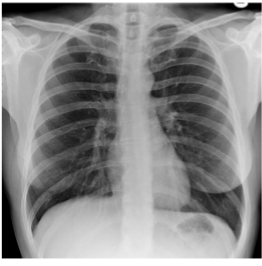

Label this CXR (10 things)

1) trachea 2) hilum- should have R and L 3) lungs 4) diaphragm 5) heart 6) aortic knuckle 7) ribs 8) scapulae 9) breasts 10) bowel gas